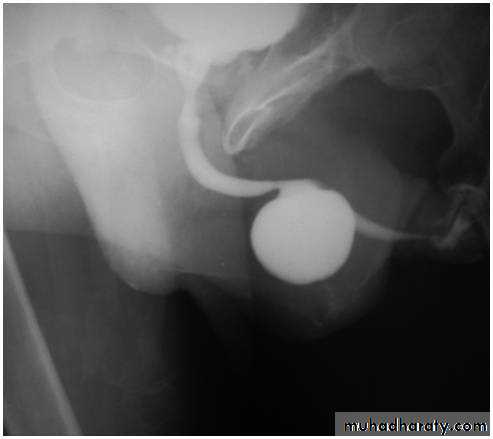

Ultrasound scan of kidneys and bladder.VCUG shows distended and elongated posterior urethra; partially filled anterior urethra; bladder neck hypertrophy; lucencies representing valve leaflets; thick-walled bladder (±diverticuli); incomplete bladder emptying; reflux (50%).

VCUG